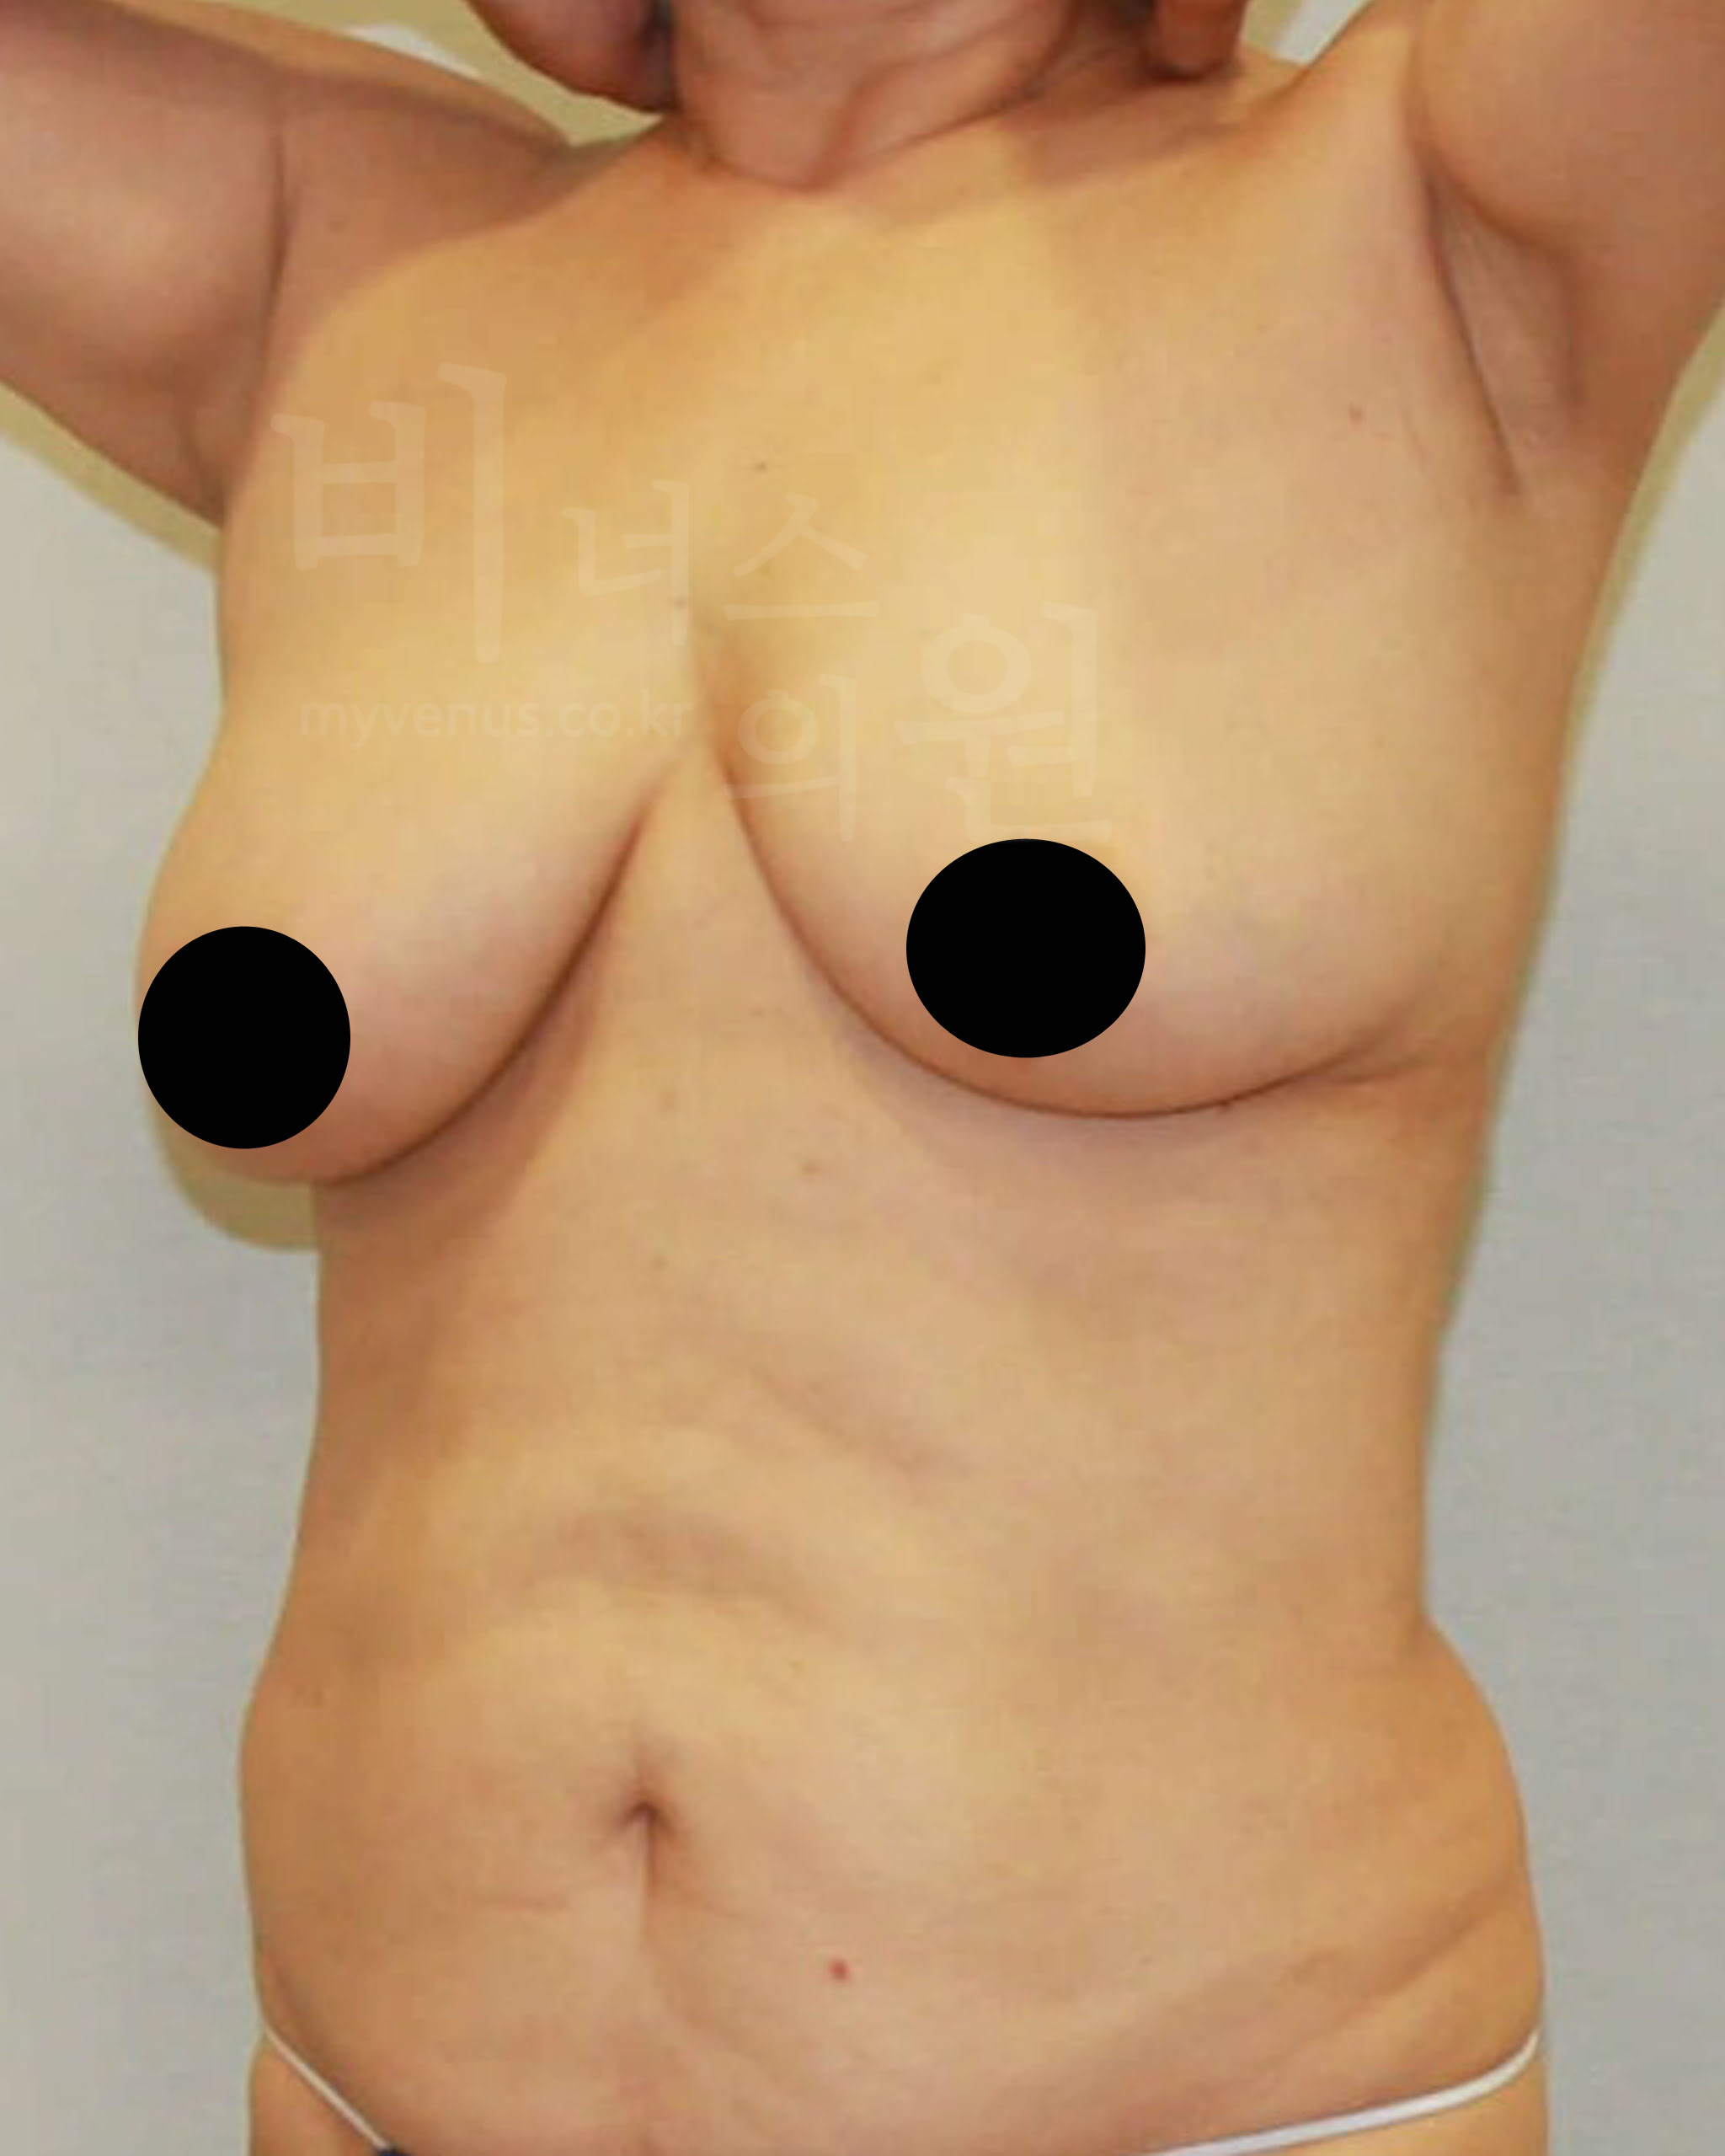

팔뚝지방흡입 전 사진

굵어 보이는 팔뚝 모습

팔뚝지방흡입 후 사진

슬림하게 날씬해진 팔뚝의 모습

처지고 큰 가슴으로 무거움을 느끼셨고 일상생활의 불편함으로 내원해주신 50대의 여성분이세요. 최대의 사이즈 감소를 기대하셨어요. 가슴 전체 축소, 부유방, 겨드랑이, 유방 옆구리 지방흡입으로 처짐, 흉터 없이 사이즈 감소에 도움을 드리기로 했어요. 가슴 절개를 하지 않고도 많은 사이즈 감소가 이루어 졌어요.

팔뚝지방흡입 전 사진

굵은 팔뚝으로 상체가 더 커 보이는 모습

팔뚝지방흡입 후 사진

날씬한 팔뚝 변화로 상체도 슬림해 보이는 모습

가슴 전체가 탄력적이며, 유륜 절개 없이도 유륜축소와 처짐이 올라 갔어요. 가슴뿐만 아니라 부유방, 겨드랑이, 유방 옆구리 지방흡입으로 군살 제거와 함께 이어지는 라인의 균형감 있고 시원해 보여요.

팔뚝지방흡입 전 사진

굵은 볼륨이 팔뚝 하방으로 쌓인 모습

팔뚝지방흡입 후 사진

예쁜 팔뚝으로 날씬하게 감소 된 모습

길었던 유방선이 가슴축소로 짧아 졌어요. 지방흡입을 통해 안전하게 처짐과 가슴 사이즈가 개선되었어요. 미세한 흡입관을 사용하여 핸드메이드 마이크로 지방흡입으로 피부의 표면이 울퉁불퉁하지 않고 자연스러운 가슴의 모습이 되었어요.